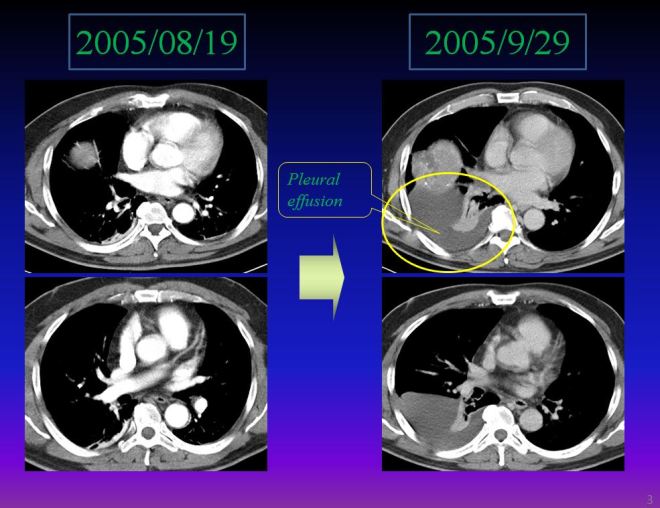

본장에서는 태음인이 색전술을 통하여서 얼마나 빨리 나빠지는가를 예를 들어서 설명해 보려고 한다. 간암은 한의원에 잘 오지 않는 병 중에 하나다. 한약이 간독성을 유발한다는 이야기를 귀따갑게 의사 선생들한테서 들은 간 계통의 환자들은 와서 설명을 듣고서도 , 그래도 나쁘다고 그렇게 당부하였는데… 하면서 선뜻 치료에 응하지 않는다. 또 한 가지 이유는 색전술 때문이다. adriamycin이 색전술에 사용되는데 이를 시행한 소음인들은 초기에는 대부분 경과가 좋고, 또 잘만 몸 관리를 한다면 완치하는 사례도 많이 있기 때문에 올 리가 없다. 그리고 색전술을 거듭하는 분들은 중간중간 효과를 발휘하기 때문에 기대감을 가지고 있다가 몇 년 지나고 아주 나빠지면 그제서야 방문하는데 이미 간이 다 암으로 뒤덥힌 상태에서 더 이상 해줄 게 없기 때문에 치료에 좋은 결과를 보기가 어렵다. 또한 색전술이 듣지 않는 태음인들은 너무 빨리 색전술 후에 암이 진행되어서 몇 달 안에 바로 사망하기 때문에 중환자실 들락거리다 사망하므로 한의원에 올 리가 없다. 처음부터 양방을 아예 포기한 사람들이 오지만 이런 분 중에는 진지한 치료보다 무어 힘 안 들이고 치료되는 방법이 없나 하면서 자연요법을 바라는 분들이 많으니 이 또한 한방치료에 적합치 않다. 그래서 내게 오는 암환자 중에 가장 많은 환자가 유방암이고 가장 적은 환자가 간암환자이다. 그래서 많은 case를 소개하지는 못한다. 그리고 태음인들은 색전술 후 너무 빨리 진행하기 때문에 손쓸 겨를이 없고 항암 독성이 체질에 맞지 않으므로 급격히 나타나서 응급으로 가서 사망하는데, 의사나 환자, 보호자나 모두 병이 원래 그런 것이라 그런거겠지 하면서 그냥 받아들이고 만다. 여기서 소개하는 환자는 내 주변 분과 가까운 지인이었는데 그 누이가 소음인으로 서울대에서 색전술을 시행받고 초기 간암이 3년 동안 재발이 없이 완치라고 판명을 받았다. 암이 걸리고 나서 주변 분들이 우리 병원으로 가 보라고 하였는데 당시 이미 집안에 양방치료로 좋은 결과가 있어서 이를 거부하였다. 나는 와서 색전술을 시행하기 전에 체질에 적합한지 여부를 좀 알고 가서 해보라고 말을 건넸는데 환자는 혹시라도 치료가 안 되면 그때 가 보겠다고 하였다. 결국 색전술을 2차 시행하고 나서 암 발견 석달 만에 내원하였다. 너무도 급격히 암이 퍼지고 복수가 차서 크게 조치할 겨를도 없이 응급으로 다시 입원하여 중환자실에서 간부전으로 사망하였다.

- M/55 체질 태음인

- 2005년8 월 간암 발견

- # 2차 TACE

- 2005/11/29 초진

- 2005/12 말 사망

위에서 보듯이 간우엽에 보이던 large mass가 대충 어림잡아도 길이로 2배가 색전술 뒤에 커졌으니 체적으로 따져 본다면 2x2x2 =8 로 적어도 색전술 이후에 40일만에 체적대비 8배로 종양이 커졌다. 또한 아래에서 보듯이 우측에 흉수가 급격히 차오르는 결과가 나타났다.

결국은 이 환자는 11월초 내원하여서 약도 써보지 못하고 응급으로 가서 중환자실에 있다가 12월말 사망을 하게 되었다. 나는 이러한 경우를 꽤 많이 보았다. 대부분 나빠진 다음에 오지도 못하고 가족이 CT를 가지고 와서 상담을 하는데, 입원해서 당장 흉수 복수가 처리가 되지 않으니 병원을 나올 수도 없고 하다가 사망을 하는 경우이다. 흉수나 복수는 암환자에게서 매우 심각한 문제이다. 암 자체가 크지 않아도 흉수나 복수가 차면 매우 좋지 않은 경우이다. 암이 비록 많이 자라 있어도 흉수나 복수가 없다면 비교적 좋은 예후로 치료가 가능하다. 왜냐하면 흉수 복수는 매우 말기적 현상이기 때문이다.